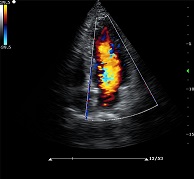

? ? ? ?C7為深圳安盛生物醫(yī)療技術(shù)有限公司新一代便攜式彩超產(chǎn)品,采用了先進(jìn)的PC平臺(tái),擁有強(qiáng)大的處理能力,優(yōu)異的圖像性能,集小巧輕便、全面的功能與輕巧流暢、特有的U型設(shè)計(jì)與一身,提供大眾新選擇。

? ?● 多種成像模式

? ? ? ?B、C、PW、CW、BCD三功、大角度偏轉(zhuǎn)成像、實(shí)時(shí)寬景成像、梯形成像(僅支持線陣)、解剖M型、彩色M型成像、組織多普勒成像、3D/4D成像

? ?● 彩色多普勒增強(qiáng)技術(shù)

? ? ? ?有效抑制彩色血流閃動(dòng)噪聲,提高血流分辨率和靈敏度